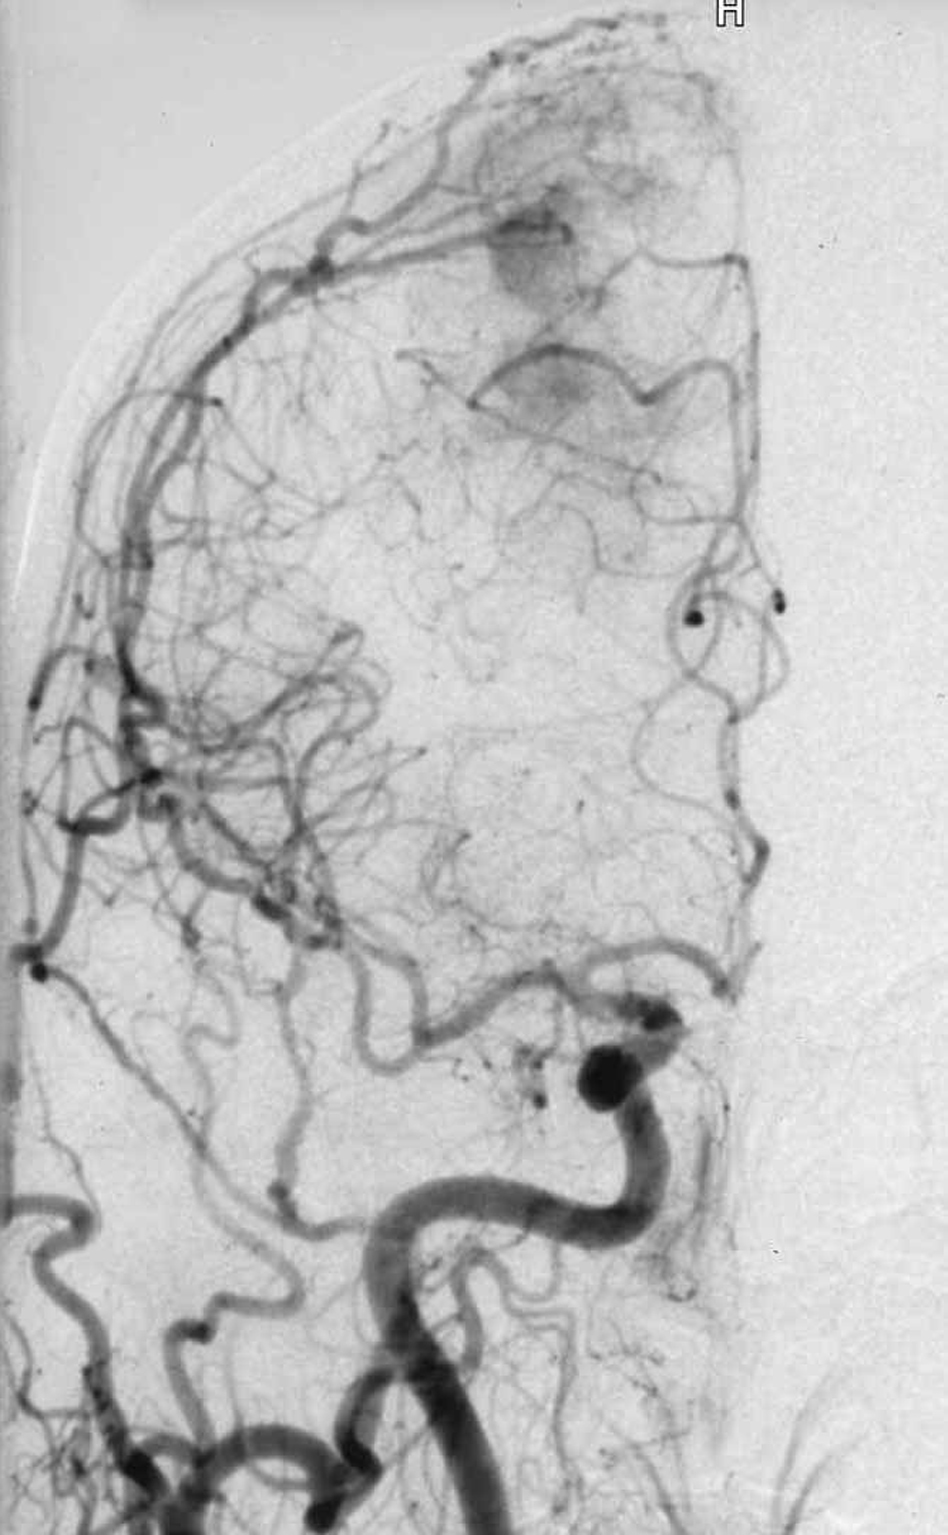

Malformazione

Artero Venosa (MAV) |